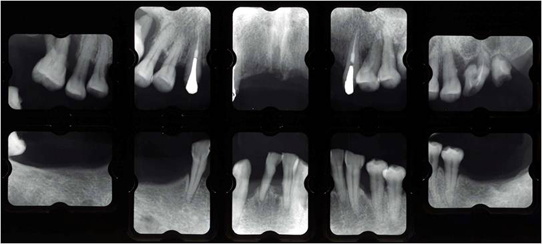

治療前

長い間虫歯、歯周病、欠損部を放置していた為、噛み合わせも含めた総合治療が必要でした。